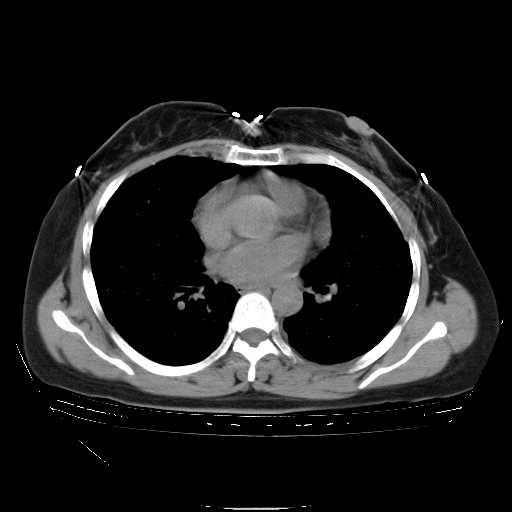

下面是今天刚刚做的,在上海治疗,吃了家属也说不清的一种药,一个月1万左右,

考虑  腺癌肺内转移,治疗较前病灶缩小、减少

肺癌并肺内转移,这种疾病治疗后在影像上看略有好转,不是很显著,但是肿瘤治疗效果影像只是一方面。

支持肺癌并肺内淋巴管炎,  原发灶小了,但转移较前片明显了.

支持右肺下叶周围型肺癌并肺内淋巴管炎,  原发灶小了,但转移较前片明显了.。

标准的细支气管肺泡癌呀!治疗后病情有所控制,也没治愈的迹象!

支持右肺下叶周围型肺癌并肺内淋巴管炎;病灶有所控制。